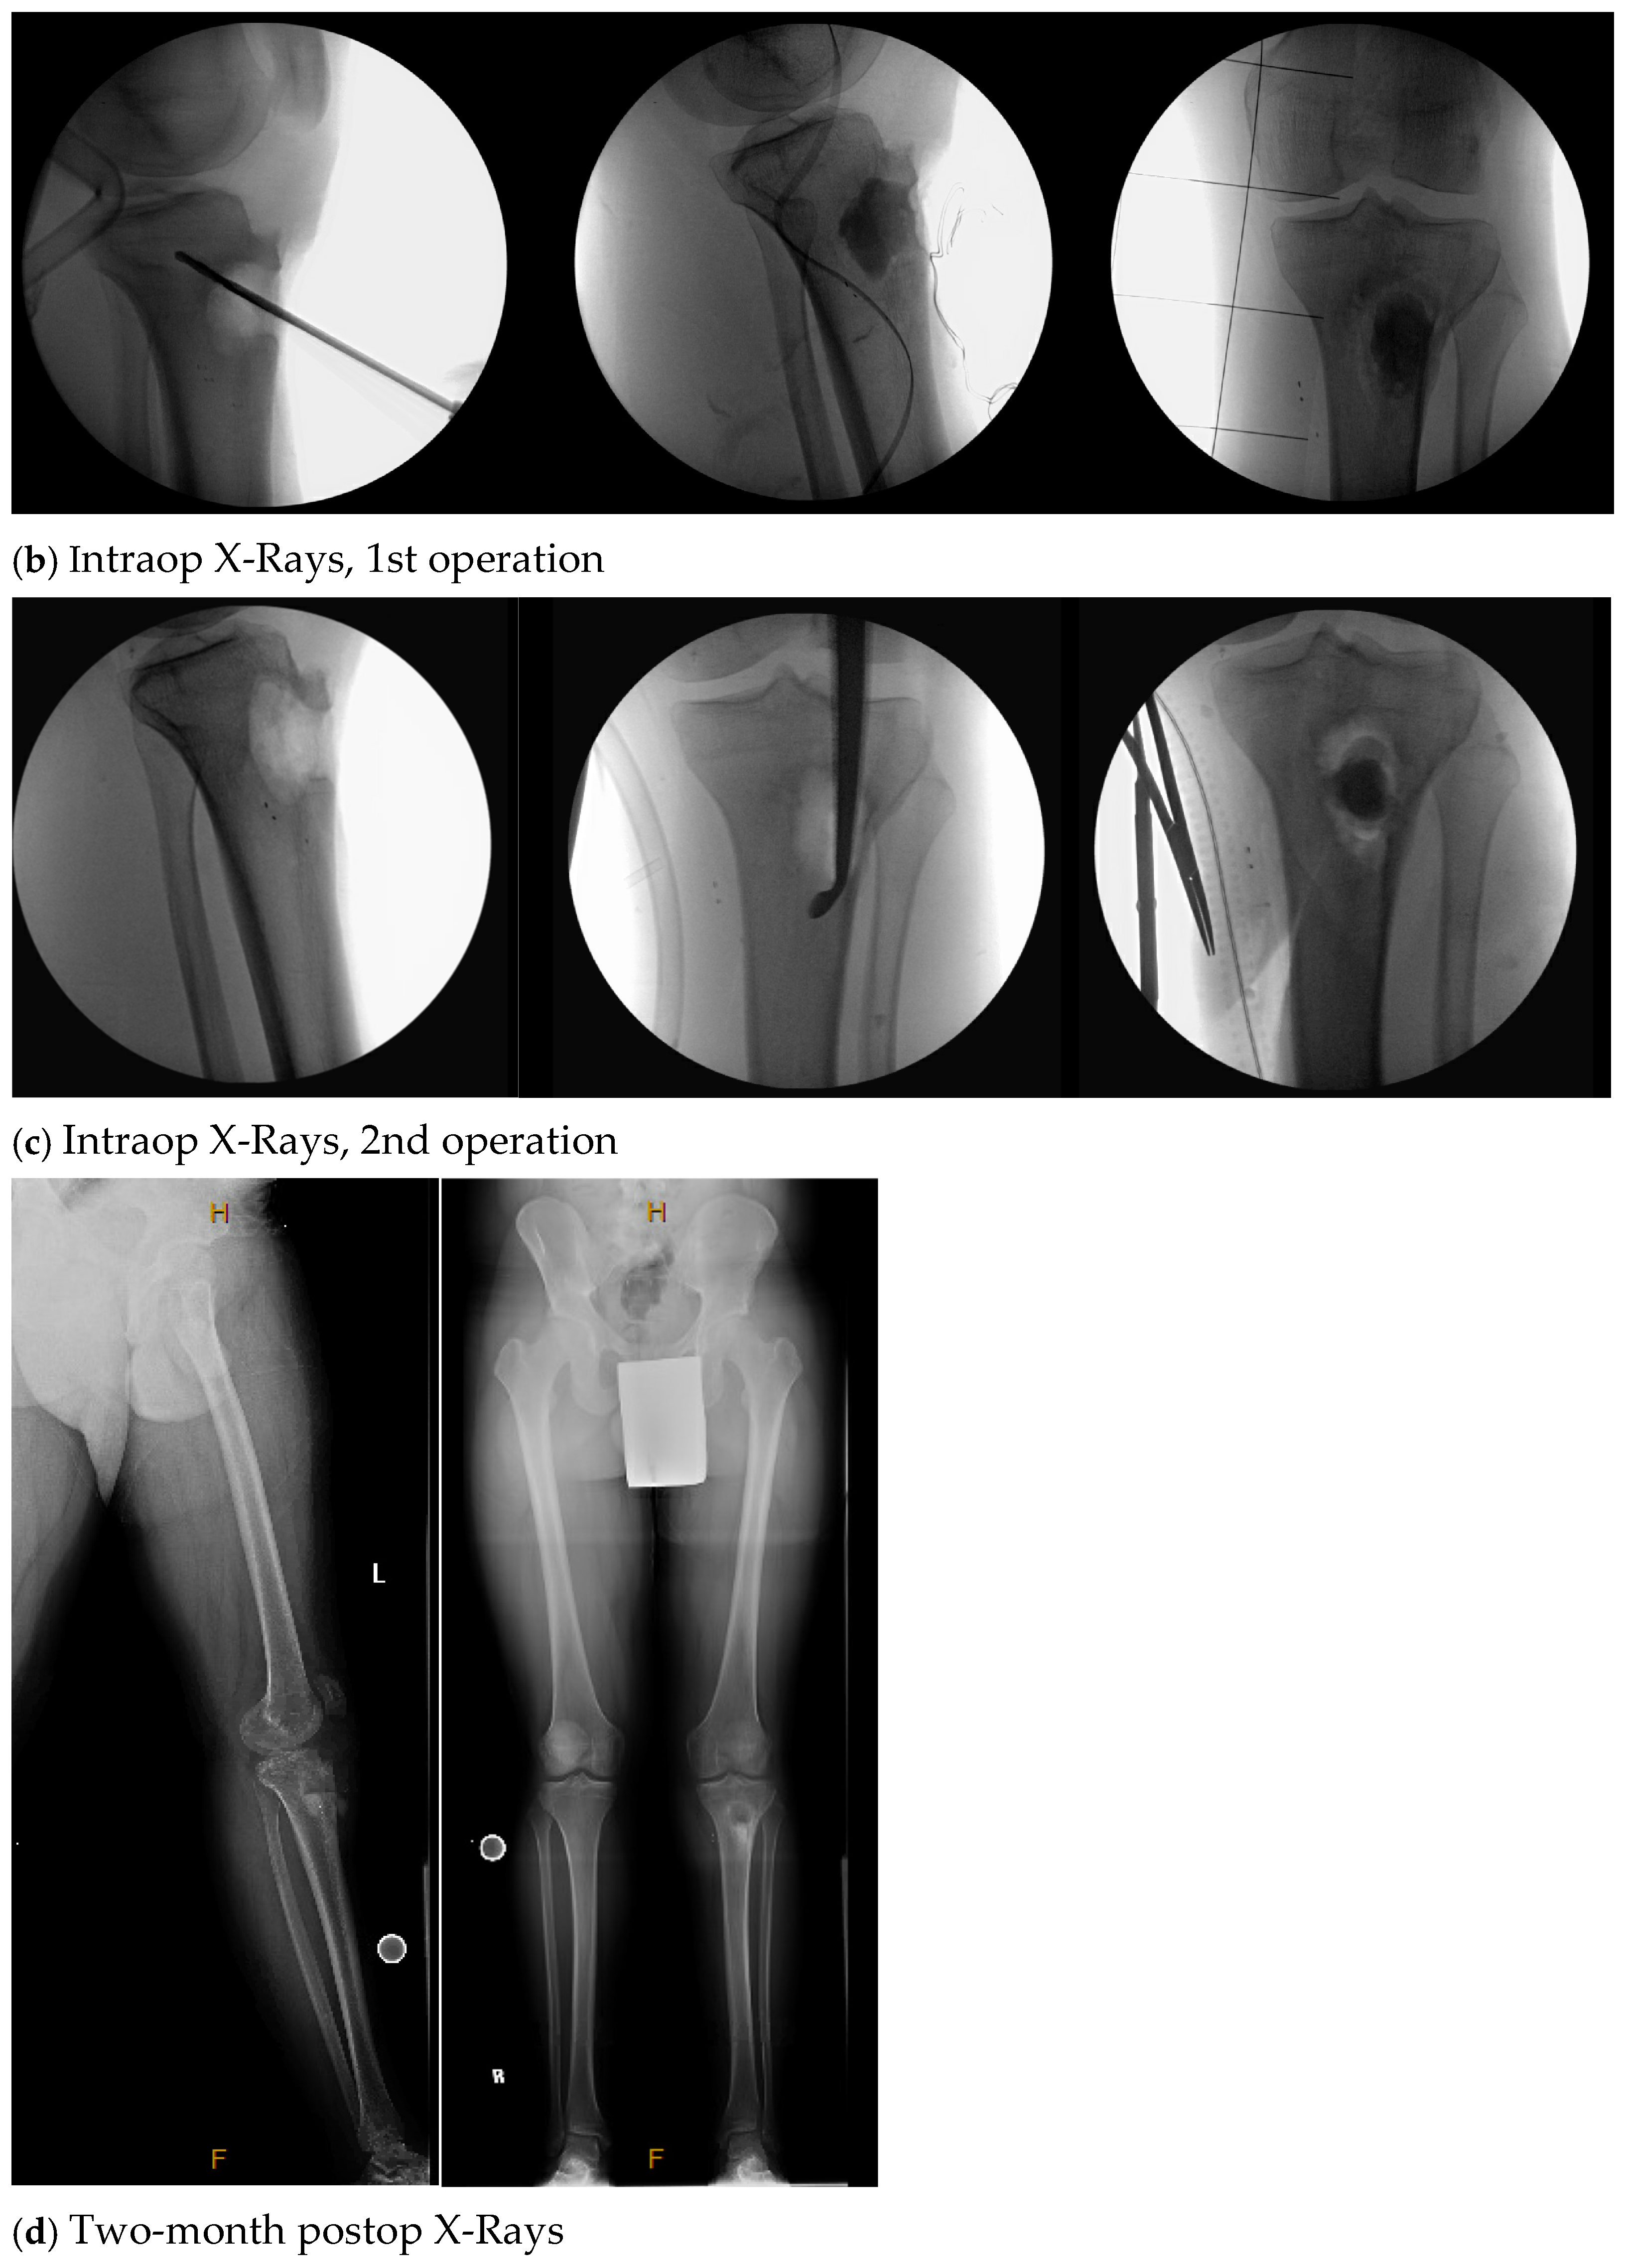

| 4. | 75 | F | Y | N | 20 | N | N | 17 | Right thigh and gluteal abscess with infected right femoral neck hardware and osteomyelitis |

| 4. | N | N | 14 | 4 | Y, clinical and lab | 107 | Negative |